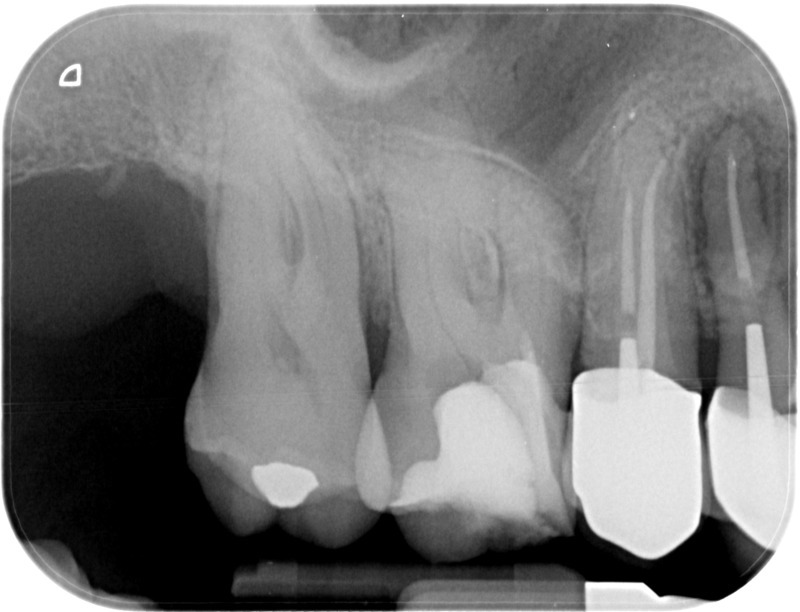

• Traitement endodontique : Sous anesthésie locale et à travers la protection d’un champ opératoire nous accédons à la pulpe de la dent à soigner, puis aux canaux de ses racines que nous devons désinfecter. Ce soin nécessite l’élimination complète de la source de contamination (souvent la carie) parfois sous une ancienne reconstitution ou une couronne qu’il faut alors retirer. Une fois le nettoyage et la mise en forme des canaux réalisés, nous les obturons de façon hermétique avec un ciment et un matériau thermoplastique appelé Gutta Percha. Ceci afin d’empêcher une nouvelle prolifération bactérienne et d’assurer le maintien de la dent dans ses structures de soutien (ligament parodontal et os alvéolaire). L’ouverture effectuée au centre de la dent sera d’abord refermée avec un pansement provisoire avant d’envisager ensemble la reconstitution d’usage : un composite, un inlay-onlay ou une couronne.

Après